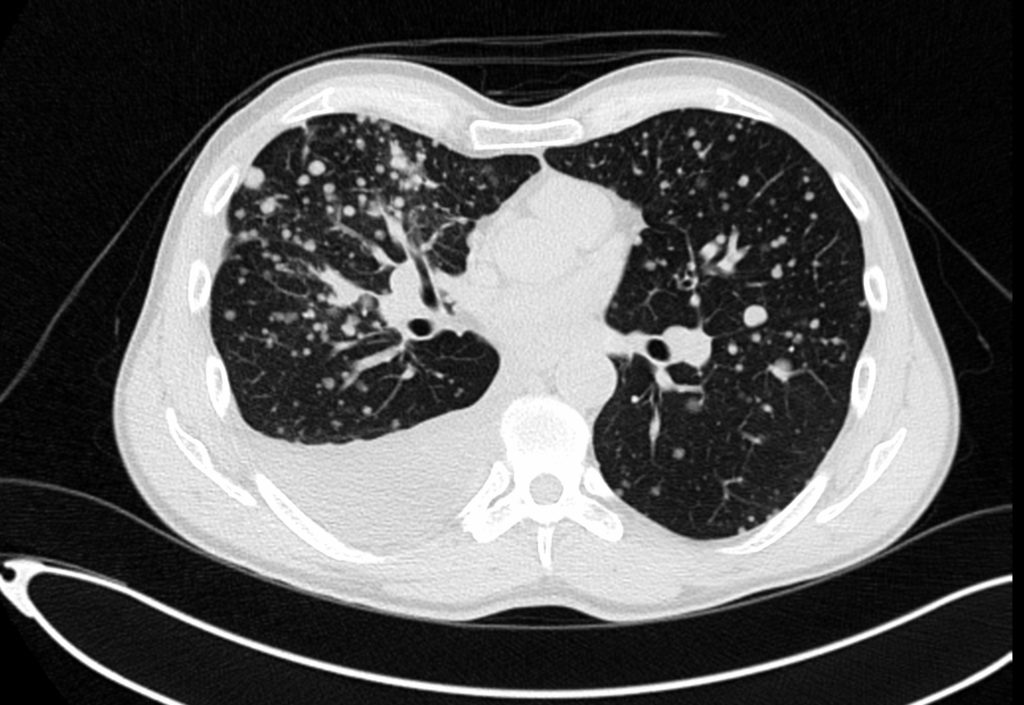

CT torace

Tomografia computerizată a toracelui determină posibile afecţiuni ale plămânilor, inimii, esofagului şi ale principalelor vase sanguine.

Afecţiunile ce pot fi descoperite la scanare sunt:

- modificări ale ţesutului pulmonar (enfizem, fibroză), infecţii, tumori, embolii ale vaselor pulmonare sau anevrisme;

- gradul de metastazare a cancerului la nivelul toracelui;

- volumetria formaţiunilor tumorale și a adenopatiilor la nivelul mediastinului și al parenchimului pulmonar;

- starea vaselor mari din mediastin, prezența maselor ganglionare, aspectul esofagului;

- angiografia aortei toracale detectează anevrisme, disecţii, coarctație;

- angiografia pulmonară detectează emboliile pulmonare, în timp ce angiografia coronariană evidenţiază starea arterelor coronare. Această investigaţie este neinvazivă, tinzând să înlocuiască angiografia prin cateterizare.